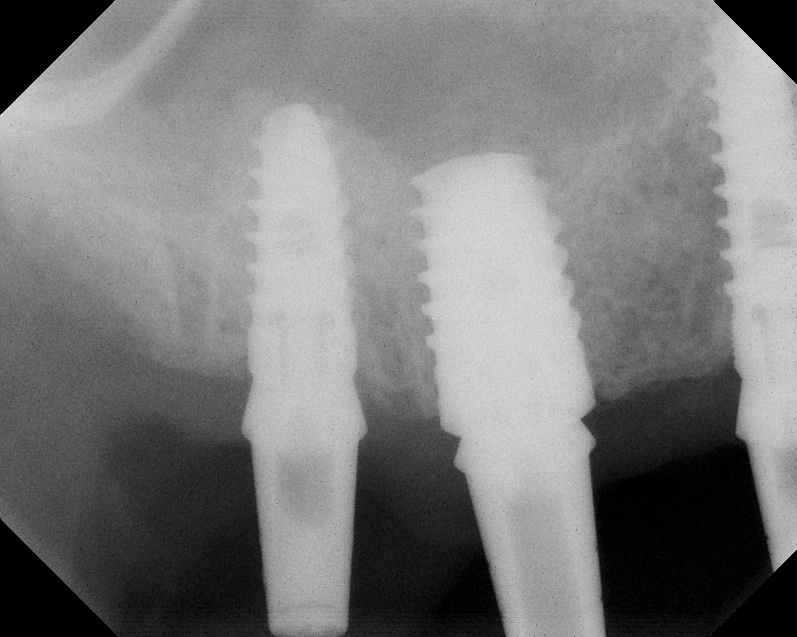

The implant is then delivered and should be well stabilized in the bone. If there is any mobility of the implant, it can either be placed a little deeper (if there is enough native bone) or the implant can be removed and the procedure aborted, in which case it would be a two-stage procedure. This should rarely occur with the tapered designed implant, even with only 2 mm of native bone. Using a bone-level platform-shifting implant (or a tissue-level designed implant) is critical, as the hard and soft tissue will establish a biologic width. If an external hex type of implant is used and the shoulder is placed at the bone level, an expected bone loss of 1.5 mm to 2 mm will occur.24 Figure 10 shows proper bone-level implant depth placement with a platform-shifting design. In this case, a 3-mm healing abutment was placed at the time of surgery to avoid a secondary uncovering surgery, but an implant-level healing abutment could have been placed instead. As can be seen, there was only about 2 mm to 3 mm of native bone height. The membrane was raised about 8 mm to 9 mm. Comparing the radiograph on the day of surgery (Figure 10) to the 6-month postoperative radiograph (Figure 11) shows no loss of native bone, as well as the positive change in appearance of the grafted bone. The 3.5-month CBCT scan (Figure 12) shows good healing of the bone with no coronal bone loss. With minimal native bone present, as in this case, the use of a non-platform-shifting or non-tissue-level implant design could be problematic. After 1.5 mm to 2 mm of crestal bone loss, an external hex designed implant could develop instability with possible implant failure. If a non-tapered implant is used and bone loss occurs during healing, migration of the implant into the sinus could potentially occur. The surgeon can use either a healing abutment or implant-level closure screw over the implant shoulder. With patients who tend to use their tongues to explore or play with the area, or if the area is under a removable partial denture, a closure screw is recommended.

Radiograph of implant N o. 3 and sinus augmentation, day of placement. There is about 2 mm to 3 mm of native bone, and the sinus has been raised about 8 mm to 9 mm.

Fig. 10

A 7-month postoperative radiograph of the restored implant No. 3.

Fig. 11

CBCT scan (Kodak 9000D) showing 3.5-month postoperative of implant No. 3 in place. Note homogeneous appearance of the bone.

Fig. 12